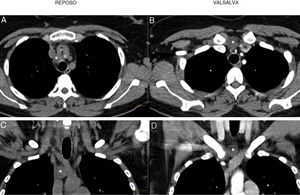

(A and B) CT scan with and without contrast, axial slices at rest and during Valsalva maneuver. (A) At rest, right paratracheal cystic lesion (*) located posterior to the trunk of the innominate veins (v) and posterolateral to the arterial brachiocephalic trunk (a). (B) In the Valsalva maneuver, the cystic lesion (*) rises through the fat of the upper mediastinum to the suprasternal cervical region, to a site anterior to the trunk of the innominate veins (v) and the arterial brachiocephalic trunk (a). (C and D) CT coronal reconstruction at rest (C) and during Valsalva maneuver (D). It can be seen that during the Valsalva maneuver, the cyst (*) rises approximately 3cm from the mediastinum to the site in the cervical region.

A 36-year-old woman consulted due to a lower midline cervical mass appearing during the Valsalva maneuver. At rest, the mass disappeared. A cervical ultrasound was performed that revealed a round, anechoic lesion measuring 2cm. The study was completed with a cervicothoracic computed tomography (CT) (Fig. 1) at rest and during the Valsalva maneuver. Presence of the rounded cystic lesion was confirmed, located at rest in the right paratracheal parenchyma, and rising during Valsalva to a site in the cervical region, not dependent on any structure. The radiological signs and the location in the right paratracheal parenchyma suggested a probable diagnosis of bronchogenic cyst. The patient was referred for surgical resection of the cyst, which was performed through a midline cervicotomy. Pathology study confirmed a bronchogenic cyst.

Bronchogenic cysts are congenital cystic lesions that typically occur in the mediastinum and in the right paratracheal or subcarinal regions. They can also appear in atypical locations, such as cervical or intrapulmonary sites.1 This case is curious due to the mobility of the cyst, which rose 3cm from a typical paratracheal site to an atypical cervical location. This mobility could be observed on CT when the appropriate maneuvers were performed, as described in other cases of cervical lesions,2 assisting diagnosis and definition of the anatomical site with a view to surgery.